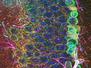

Pain Pathway

The brain's emotional (distress caused) pain pathway identified – offering new targets for developing pain medication

This group of neurons (green) within a subsection of the brain's thalamus are a newly discovered part of the circuitry that links the physical sensation of pain to the emotional response. It's the emotional aspect of pain – the distress it causes – that teaches an animal to avoid potentially painful situations. Indeed, when carefully targeted genetic techniques were used to deactivate this particular group of neurons in mice, the animals could still sense the pain of heat or pressure but didn't learn to avoid the source of the stimulus. By contrast, when these neurons were artificially activated, the mice exhibited distress and avoidance behaviours even in the absence of actual pain stimuli. The identification of this emotional pain pathway offers new targets for developing different forms of pain medication that might be especially useful for people with increased sensitivity to pain or with chronic and distressing pain disorders.